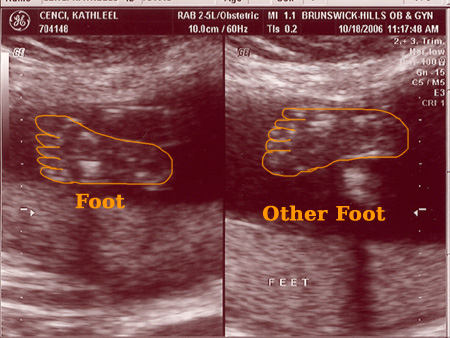

On October 18, 2006 we had the second sonogram. The baby is growing well. It was moving quite a bit while we were watching. It is amazing to actually see feet, arms, ribs, the spine, we even saw it sucking it's thumb. Check out the photos below. Each one is clickable which will bring you to labeled versions to help you identify what you're looking at. Enjoy!

Sonogram #2 - Image 4

Click on any/all of the photos above to see more. The links will give you full resolution photos and labeled versions. The labeling is my best guess as to what your looking at. We saw much more on the monitor, the motion version was awesome.